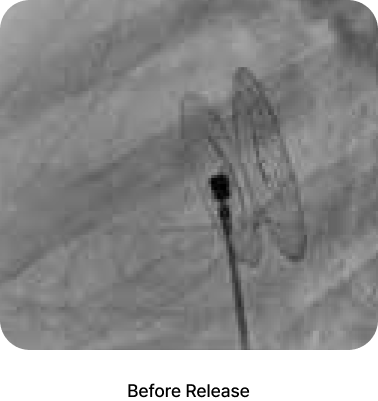

360 flexible rotation, accurate positioning and safe detachment

The CeraFlex™ wire loop connection system offers an accurate final positioning without the adverse tension or stress caused by the delivery cable.